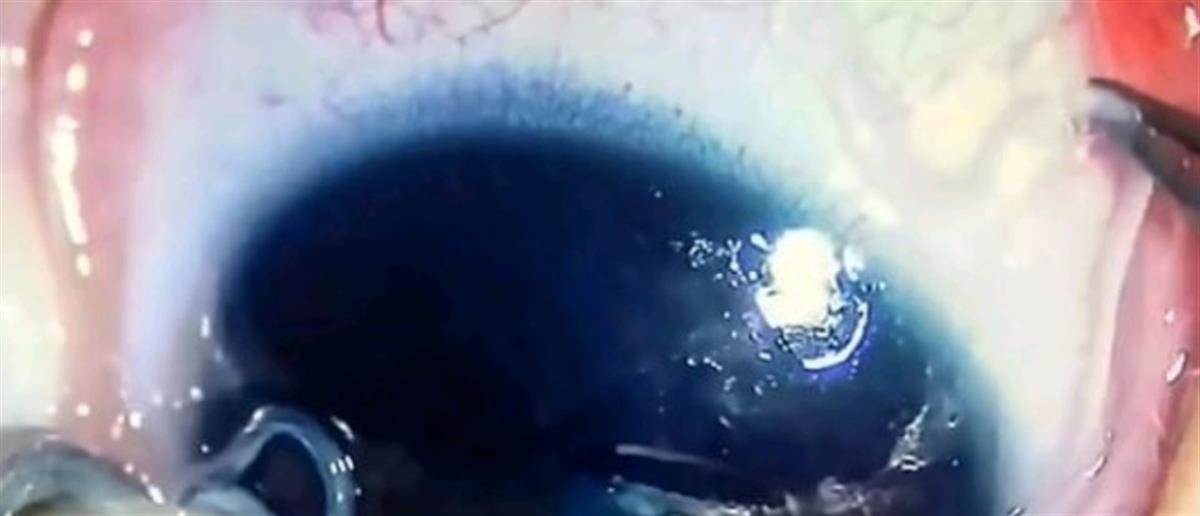

Σοκάρουν οι εικόνες από νοσοκομείο στην Κίνα όπου γιατροί αφαιρούν ζωντανά σκουλήκια από το μάτι ενός βρέφους!

Οι γιατροί, κατά τη διάρκεια της εξέτασης, ανακάλυψαν πολυάριθμα σκουλήκια που «γλιστρούσαν» στην επιφάνεια του βολβού, καθώς και στο εσωτερικό του βλεφάρου.

Τα σκουλήκια πιστεύεται ότι ανήκουν στο είδος «Thelazia callipaeda» – ένα παράσιτο που ανακαλύφθηκε για πρώτη φορά στην Κίνα πριν από περισσότερα από 100 χρόνια. Τα παράσιτα, αυτά, συνηθίζουν να «ζουν» στα μάτια των σκύλων, των γάτων αλλά και των ανθρώπων.